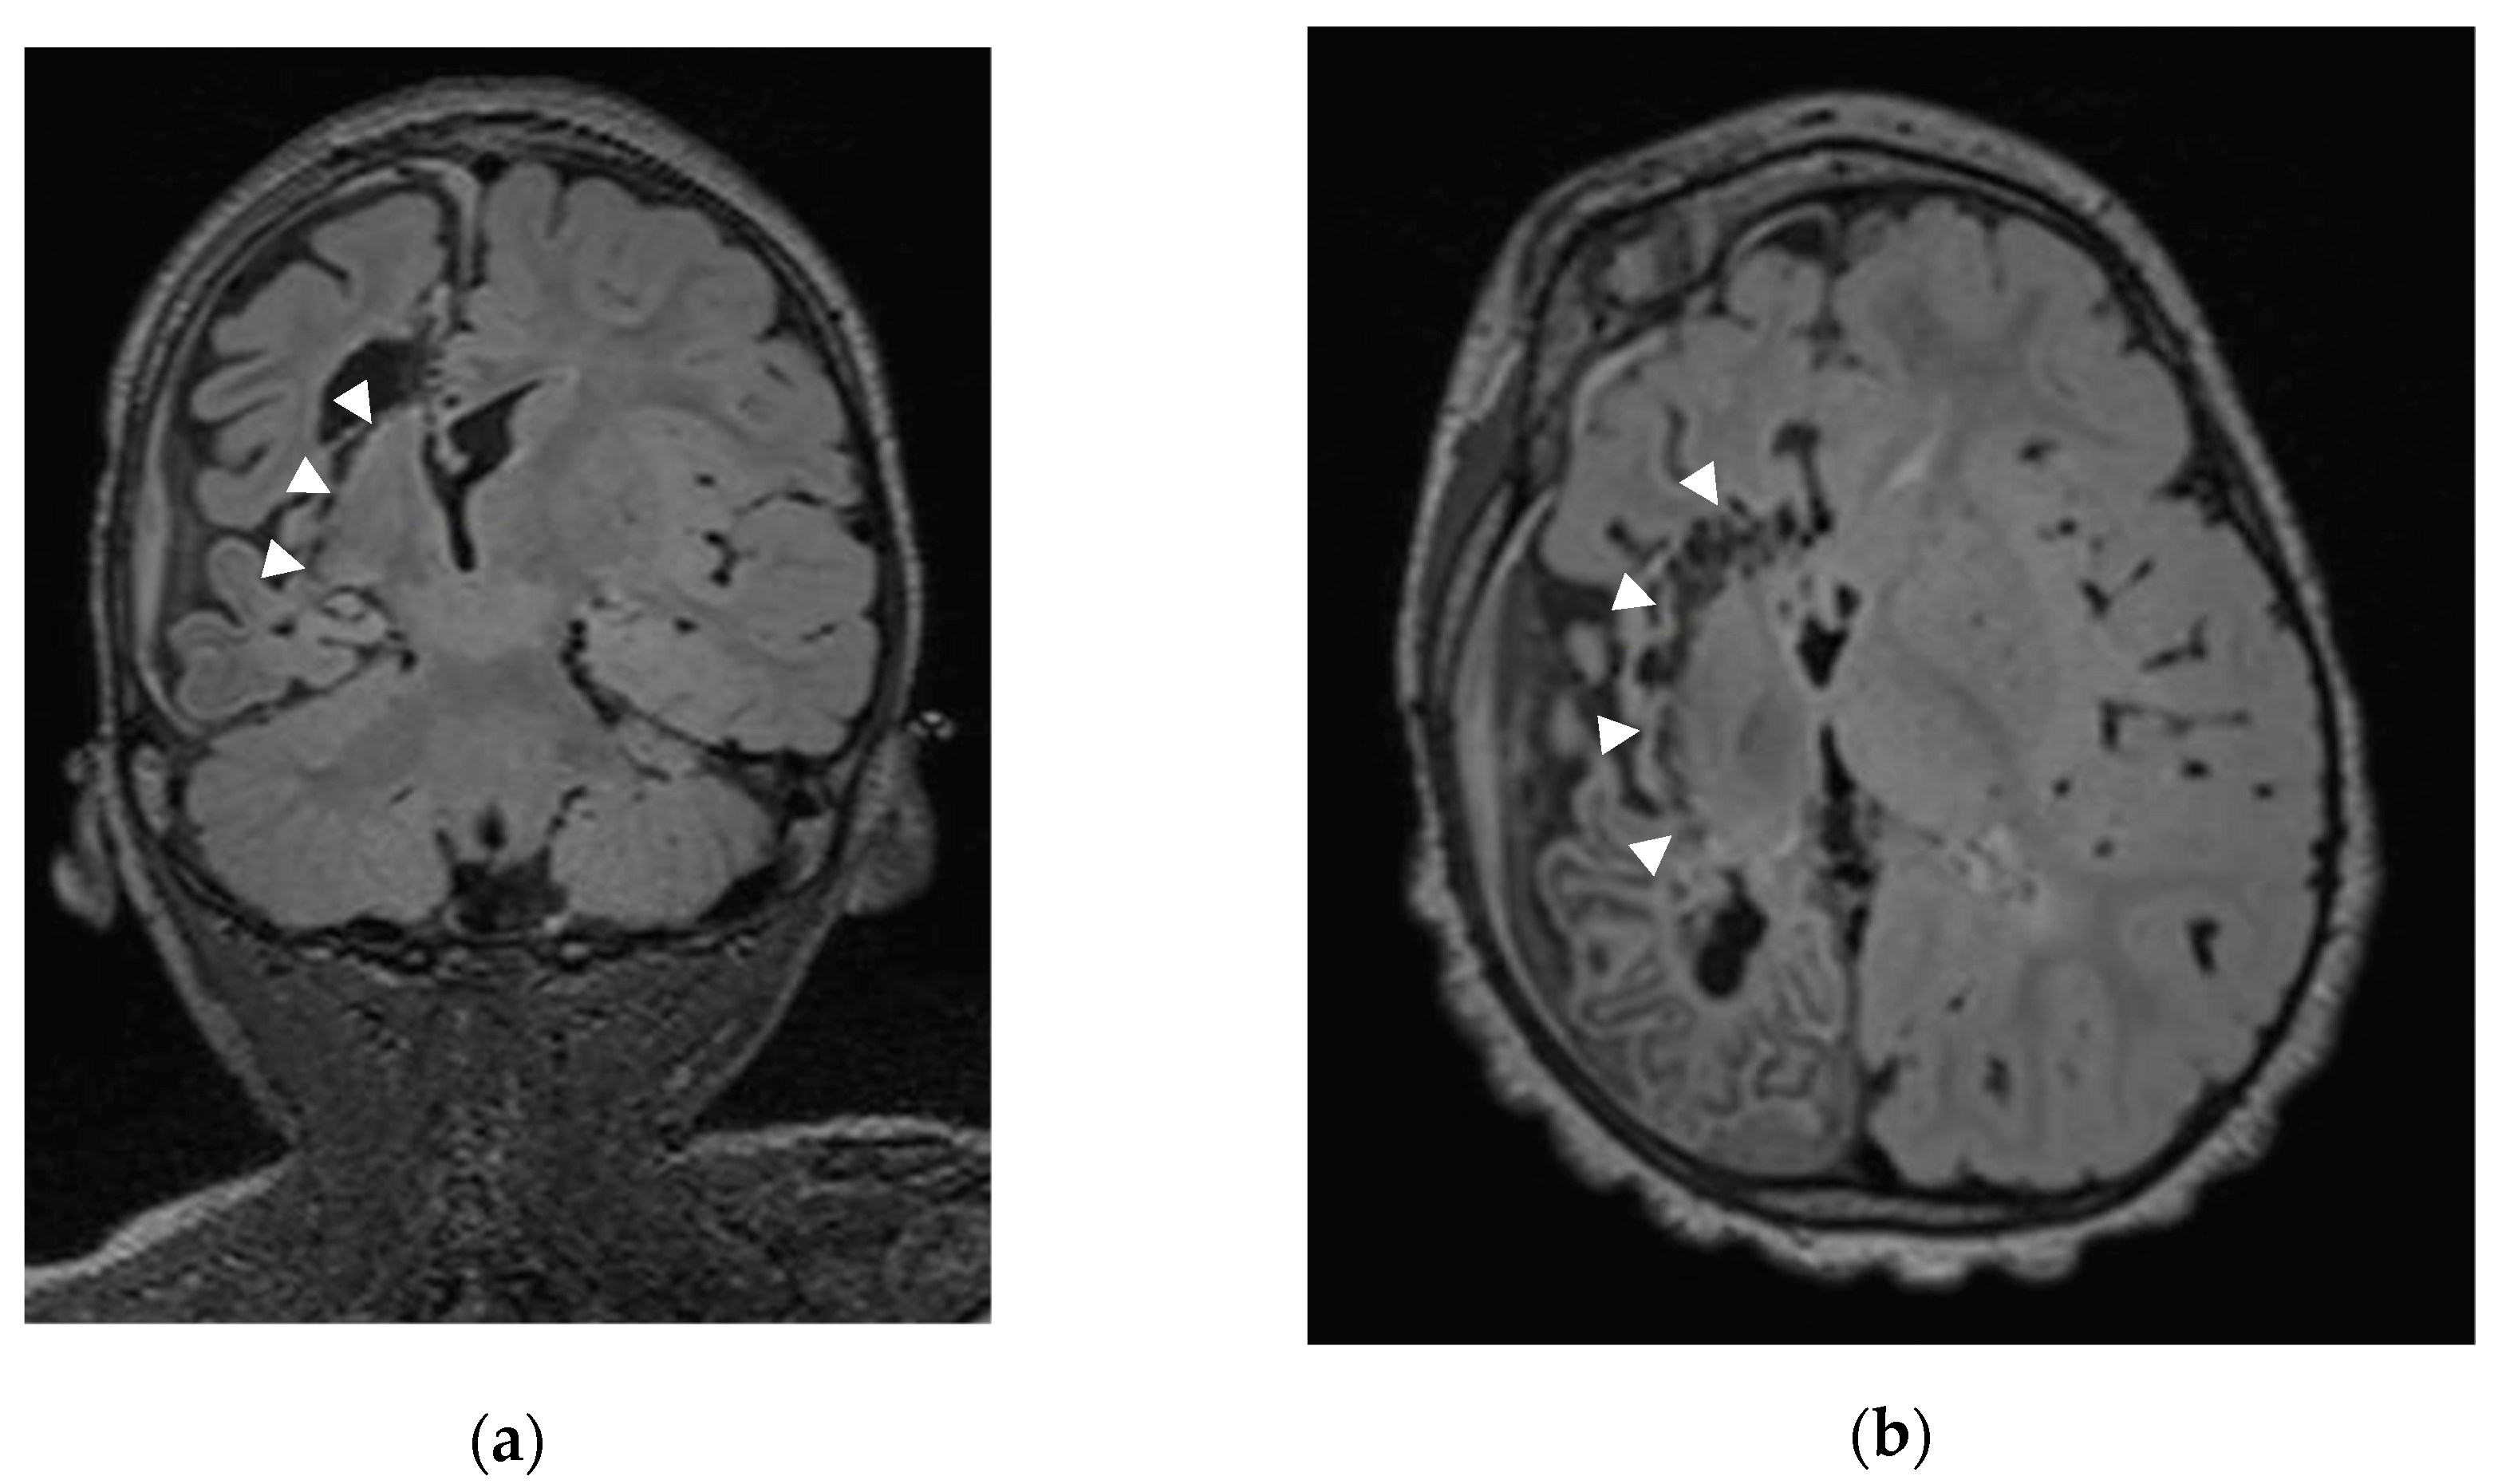

2.2. Sub-Insular VPH Method Description (Figure 1)